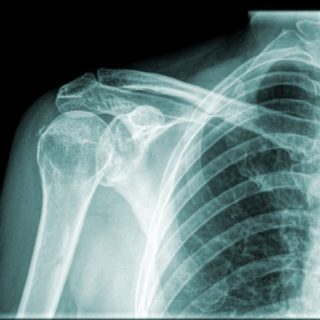

Травмы

При переломе имеются внешние признаки — асимметрия обеих ключиц, деформация кожи над местом травмы

Перелом ключицы практически всегда вызывает внешнюю деформацию кости, так как она одна из наиболее тонких в составе скелетного аппарата человека. К тому же ключица окружена сильными мышцами, спазм которых при травме приводит к сдвигу костных отломков. В месте перелома чувствуется острая болезненность, ткани вокруг него опухают с каждым часом всё больше. При надавливании, попытке сделать движение рукой или поднять ее боль усиливается. Если отломок кости сдавливает 3 или 4 позвонок, появляются такие симптомы, как онемение за ухом, «отяжеление» языка, комок в горле.

Вывих ключичной кости также сопровождается ее смещением, отеком и болью при движении. Человек не способен пошевелить плечом, высоко поднять, низко опустить или отвести в сторону руку. При нажатии ключица может встать на место, однако ее положение неустойчиво.

При первом обращении делают рентген, чтобы проверить целостность костей

При подозрении на любое заболевание пациенту необходимо как можно скорее обратиться за медицинской помощью, чтобы пройти обследование и получить необходимое лечение. Это особенно важно, если речь идет о возможной травме ключичной или плечевой кости.

Основной способ диагностики травм костно-мышечного аппарата – рентгеноскопия. Рентгеновские снимки позволяют врачу с абсолютной точностью определить место и характер смещения, вывиха или перелома ключичной кости, а также убедиться в правильности проведенной коррекции и в динамике наблюдать процесс восстановления поврежденных тканей. В последние десятилетия с этой целью используются также методики ультразвукового исследования, магнитно-резонансной и компьютерной томографии (УЗИ, МРТ, КТ). Они позволяют ставить диагнозы не только при травматических повреждениях, но и при других видах патологических нарушений, являющихся следствием внутренней дисфункции различных систем организма.